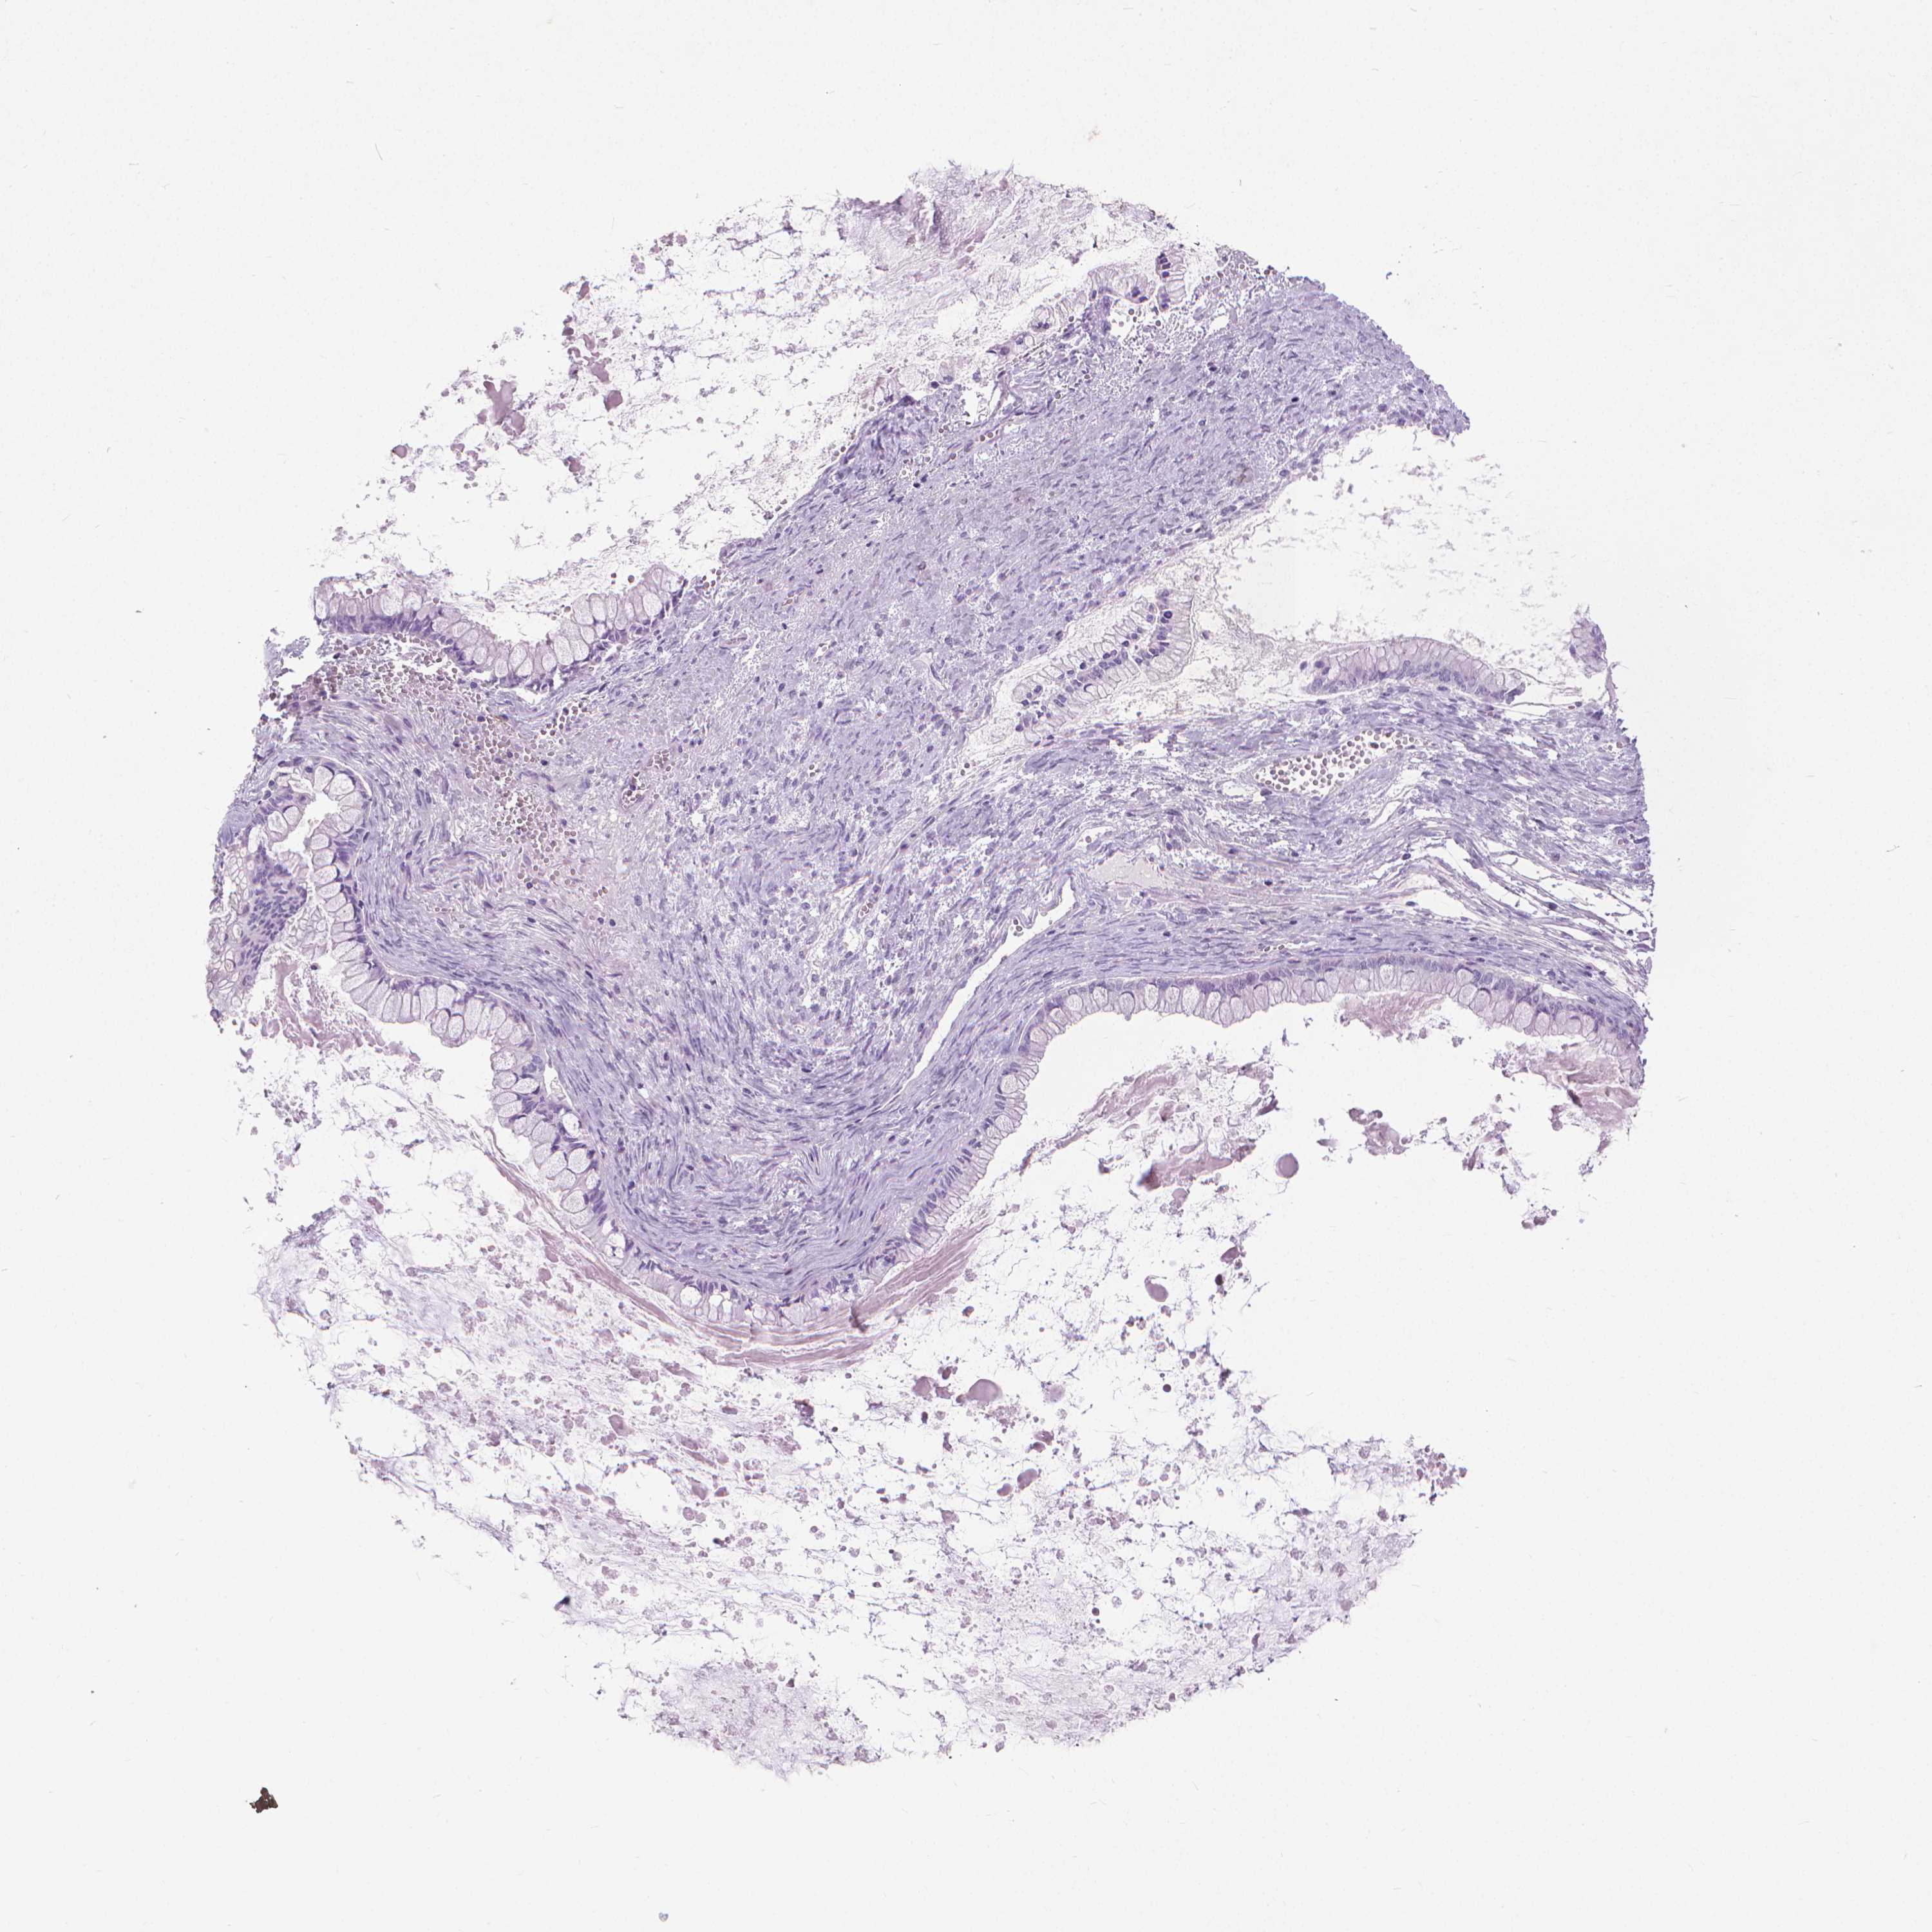

OVARIAN CANCER - Protein expressioni

A mouse-over function shows sample information and annotation data. Click on an image to view it in a full screen mode. Samples can be filtered based on level of antibody staining by selecting one or several of the following categories: high, medium, low and not detected. The assay and annotation is described here.

Note that samples used for immunohistochemistry by the Human Protein Atlas do not correspond to samples in the TCGA dataset.

Antibody stainingi

Antibody staining in the annotated cell types in the current human tissue is reported as not detected, low, medium, or high, based on conventional immunohistochemistry profiling in selected tissues. This score is based on the combination of the staining intensity and fraction of stained cells.

Each image is clickable and will lead to virtual microscopy that enables deeper exploration of all samples and also displays staining intensity scores, fraction scores and subcellular localization as well as patient and tissue information for each sample.

Antibody HPA059479

Antibody CAB000027

Cystadenocarcinoma, serous, NOS

Cystadenocarcinoma, mucinous, NOS

Carcinoma, endometroid